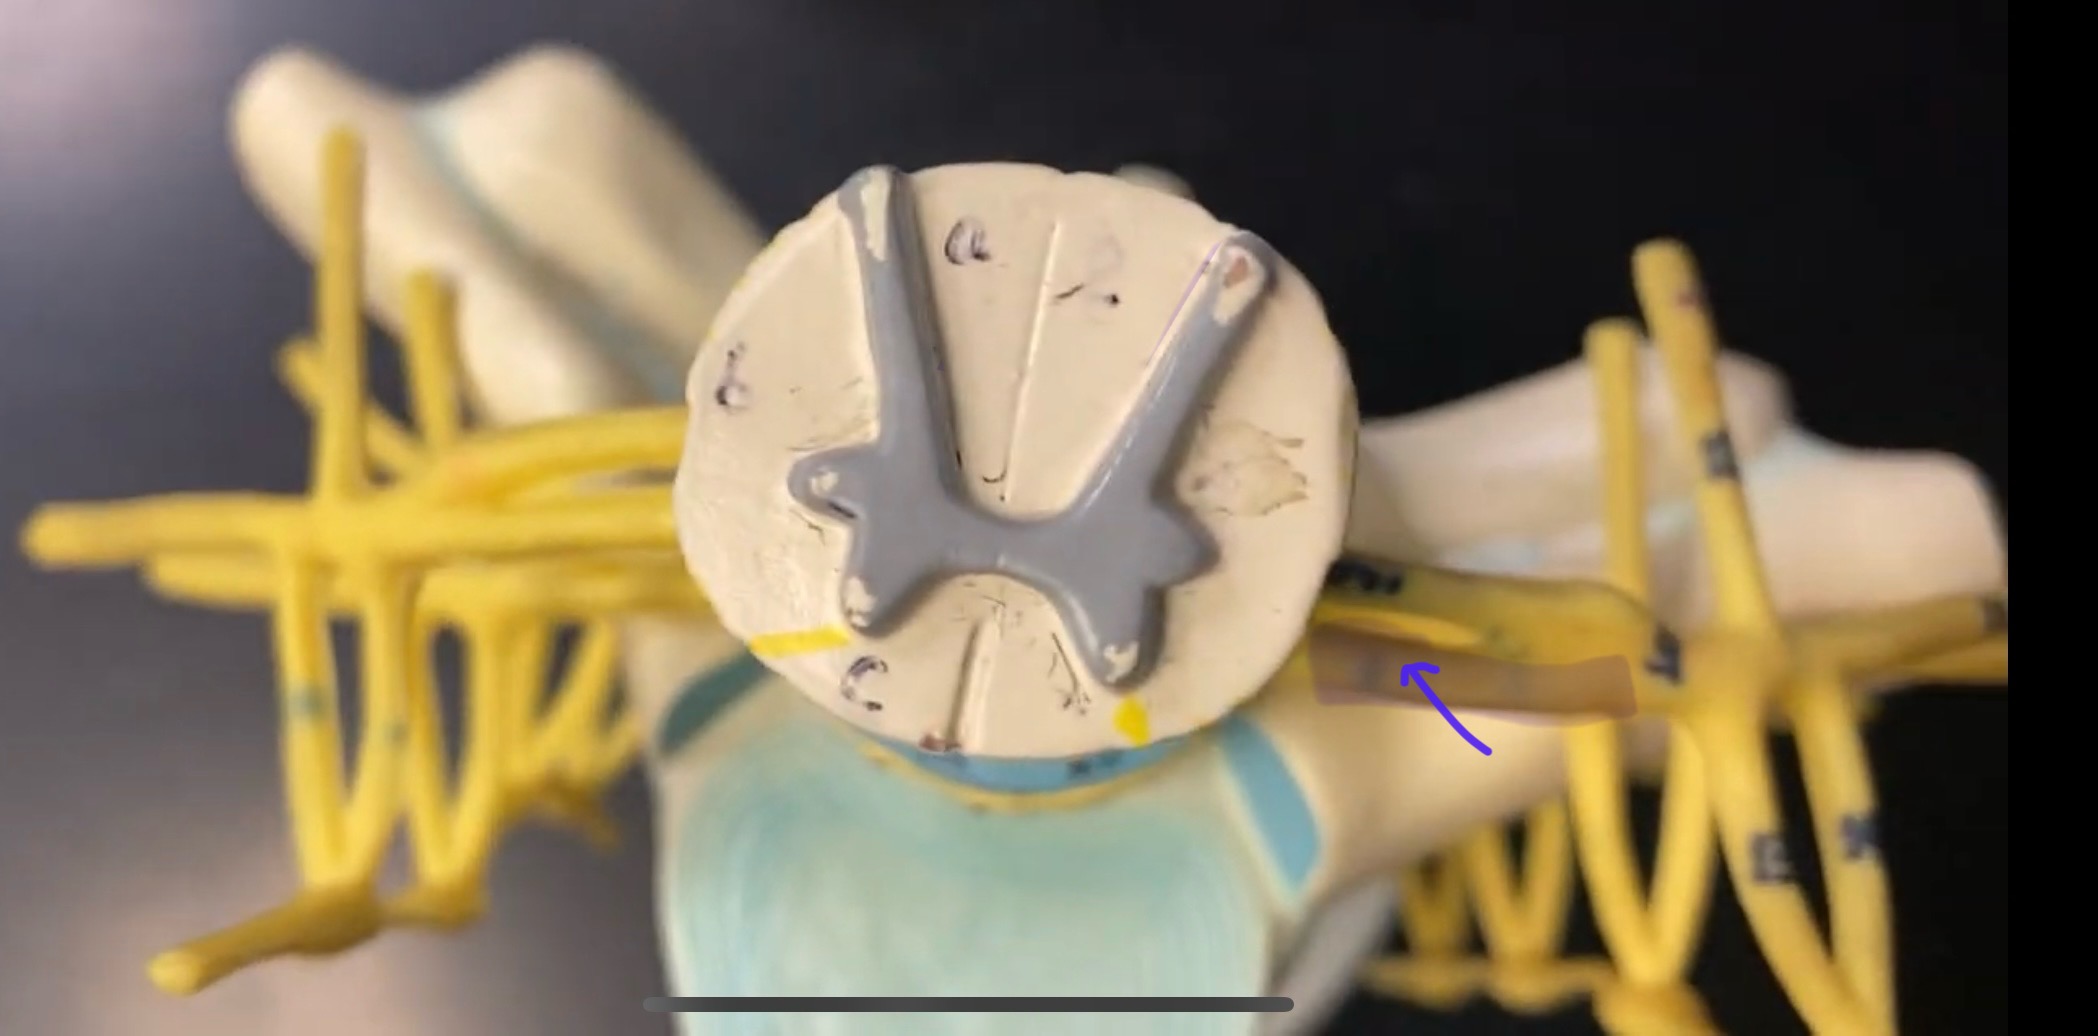

What is the groove here?

anterior median fissure

posterior median sulcus

posterior (dorsal) horn

posterior (dorsal) horn; R—>L

anterior (ventral) horn

lateral horn (selected models)

gray commissure

central canal

anterior column

lateral column

posterior column

white commissure